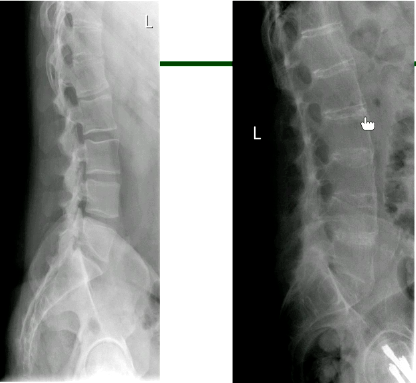

What is axial spondyloarthritis?

An umbrella term for types of inflammatory arthritis that primarily affect the spine and the sacroiliac (SI) joints that connect the lower spine to the pelvis

Key facts about axial spondyloarthritis

Difference between x-ray